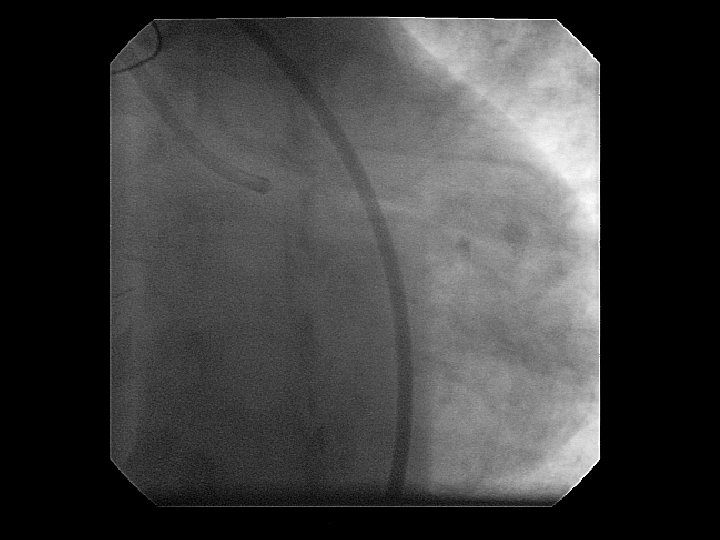

Coronary Dissection

Think first: Use force Last